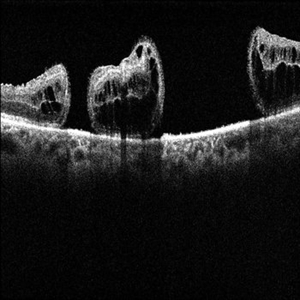

Retinoschisis

A 14-year-old male patient was admitted for visual assessment. Visual acuity s/c in the right eye and 20/80 in the left eye. According to family members, he reported low vision since childhood. He had already undergone photocoagulation treatment at another service for which he had a diagnostic hypothesis of Coats' disease. Laboratory tests were requested (HIV, TOXO, TOXOCARIASIS, ACE, VDRL, PPD). In the evaluation, there was significant exudation in the posterior pole, some vascular irregularities in the right eye. In the left eye, there is retinoschisis affecting the entire posterior pole and the nasal region to the optic disc, macula with a characteristic chariot-wheel appearance, well exemplified by OCT-A (Structrure Deep: IPL - 25, OPL - 25).

Photographer: JEFFERSON R SOUSA - Study Center and Ophthalmological Research Dr. Andre M V Gomes, Institute Dr. Suel Abujamra São Paulo-Brazil

Imaging device: Optical coherence tomography system Optical Coherence Tomography system OCT CIRRUS 5000, Line Protocol, HD 21 line. Cirrus 5000 does not do a wide-angle tomographic image. (Structrure Deep: IPL - 25, OPL - 25).

Condition/keywords: Coats' disease, retinoschisis